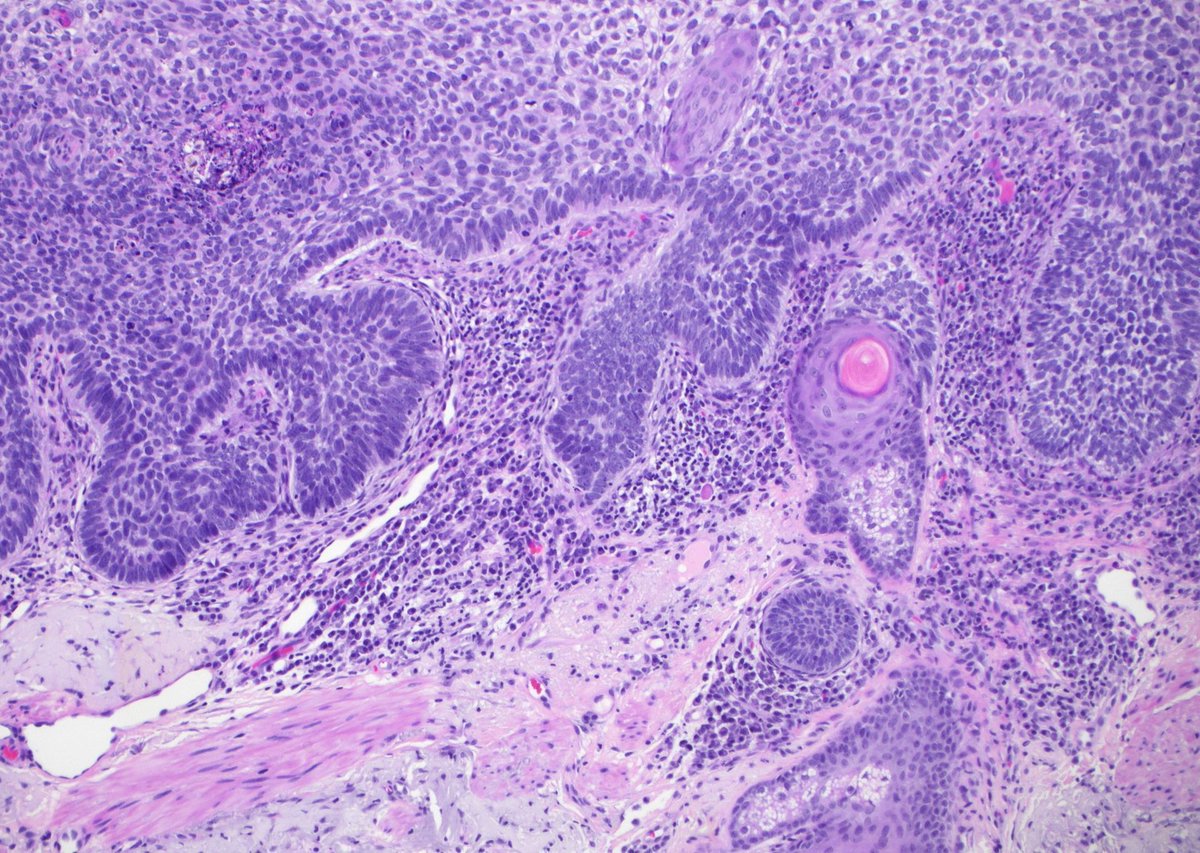

75 yo M. Big dorsal hand SCC with BONE invasion & multiple lymph node metastases. Why is this SCC acting so aggressively?!? Answer ✅ https://t.co/nVA7OgXMzh Digital slides: https://t.co/AMhtDEQjqA

#pathology #pathologists #pathTwitter #dermpath #dermatology #dermtwitter